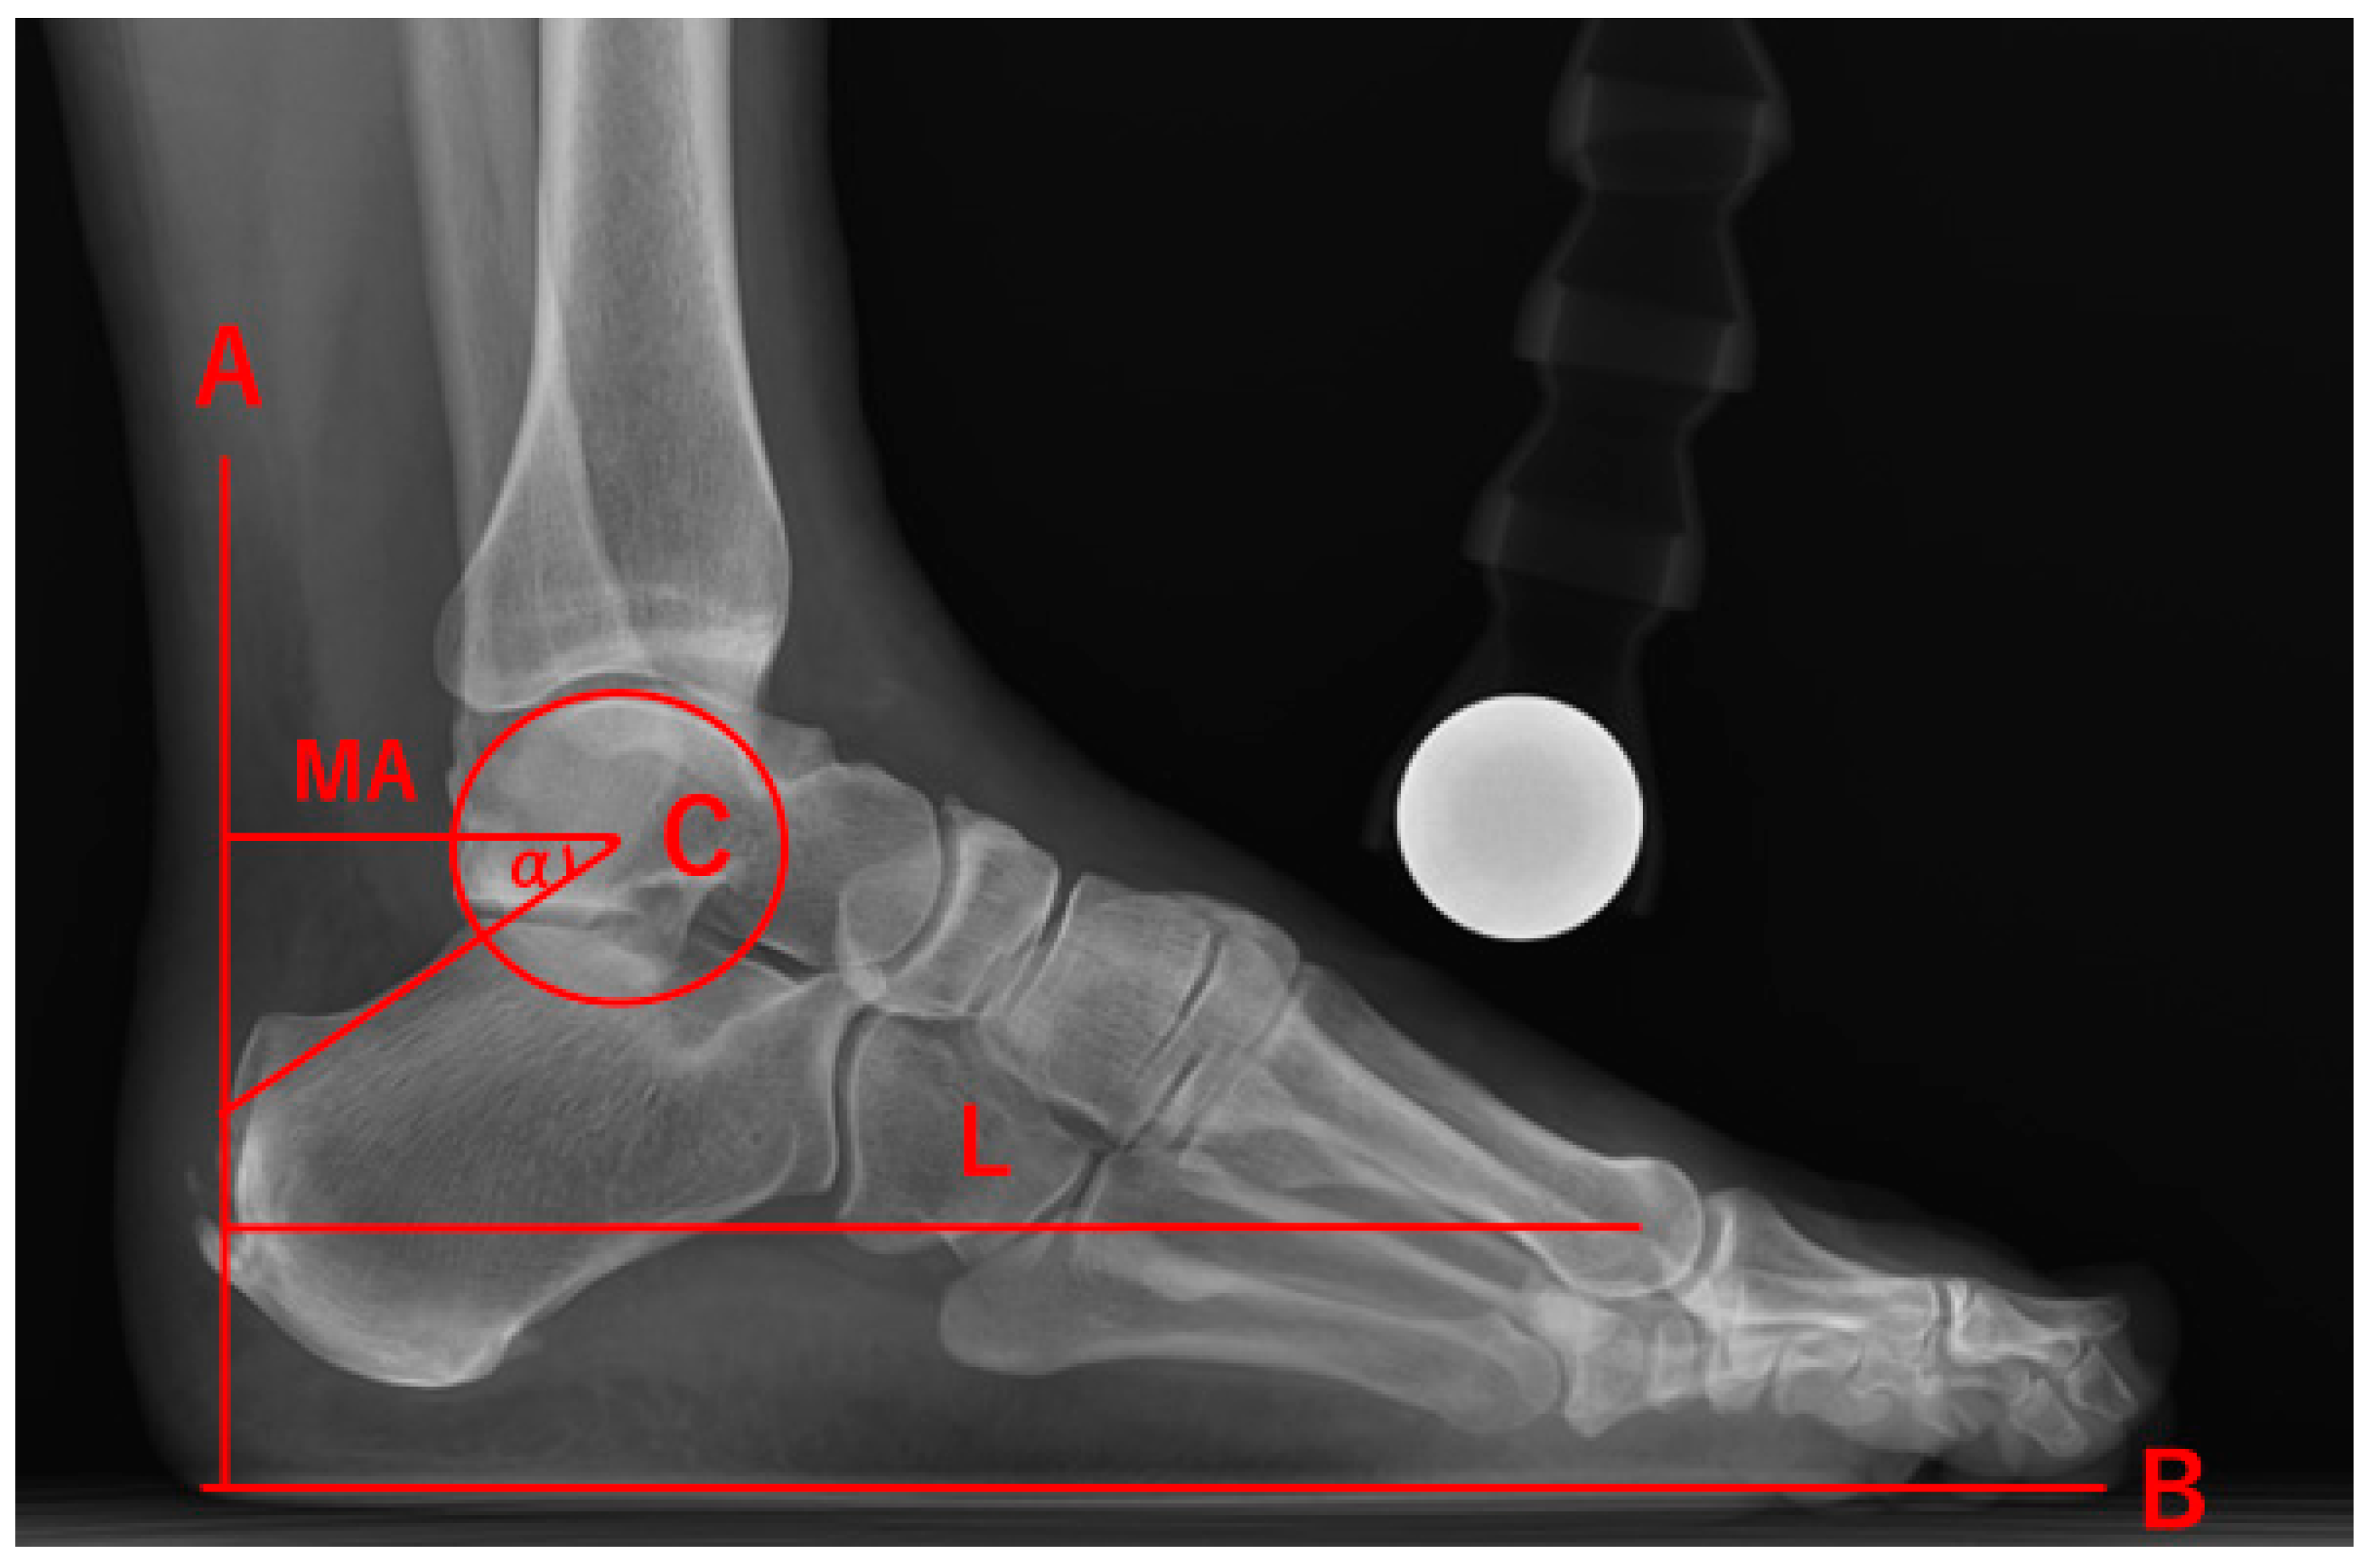

Effects of Achilles Tendon Moment Arm Length on Insertional Achilles Tendinopathy